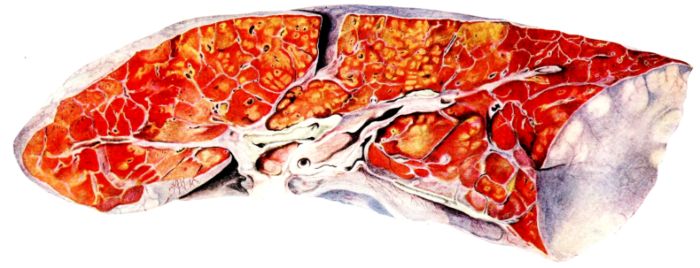

FIG. XIII. AUTOPSY NO. 96. RIGHT LUNG. A WATER COLOR DRAWING OF A GROSS LUNG IN THE ACUTE STAGE. NOTE THE SIZE OF THE LUNG, THE HEMORRHAGES ON THE PLEURAL SURFACE, AND THE BLUE AREAS OF CONSOLIDATION.

FIG. XIV. AUTOPSY NO. 96. LEFT LUNG. NOTE ITS SIZE AND THE PATCHY CONSOLIDATION.

19The lungs are extremely voluminous (12, 17) due in part to an accumulation of liquid within them. This finds its way into the trachea and completely fills the latter structure with blood-stained, syrupy fluid, with purulent material, or with a mixture of these (2, 90, 107, 157, 162). At first the pleural surface is smooth and often quite even, but on closer inspection, a minute granulation is suggested. In many cases even close examination does not allow the conclusion that an exudation of anything but serum has occurred through this membrane, except in localized foci. These foci more frequently involve the interlobar pleura and that of the lower lobes (112, 143). The volume of the lungs, often great enough to obliterate the pericardial area, is one of the two most characteristic features of the external examination. The other feature is their color. Small, bright red hemorrhages may occur anywhere. The larger patches are the most striking. Violet, purple, or dark brown areas, irregular in shape and distribution, are more frequently found on that portion of the pleura over the lower two-thirds of the lung. Between the deeply colored zones, there are pale pink areas which involve the lowermost edge to the least degree, the anterior margin somewhat more, and the apex of the lung most of all. The darker portions just referred to may project above the surface and may be circumscribed, resembling huge, fresh hemorrhagic infarcts (41, 108). The alveolar walls are not seen through the pleural surfaces in these darker zones. The pale pink areas, usually at the level of the more intensely colored zones, may be elevated and the dilated air sacs are distinctly made out through the pleura (Fig. XIII). At the hilum, the lymph glands are large and soft. When cut, fluid escapes and is often blood-stained. The cross section may present a distinct, diffuse, hemorrhagic appearance (162). At the hilus, too, the lymphatics, distended here and there over the surface of the pleura, are most affected. The congested bronchial mucous membrane and the exudate in these structures has been described.

After removal, the lung retains its shape, but is more flaccid than the consolidated lung of lobar pneumonia. It cuts with very little resistance and immediately a large amount of a syrupy, pink fluid escapes and obscures the entire area. With the fluid scraped away, the variations in the consistency of the lung become visible. The pale areas around the borders and chiefly at the apex in which the air sacs are discernible with the naked eye, sink slightly below the remainder of the surface, and the pleural edge inverts. The individual lobules of the lung in these areas are more conspicuous than normal, because the interstitial tissue bearing the lymphatics and vessels, as well as that around the bronchi and larger blood vessels, does not lose its edematous appearance as quickly as the alveoli (40, 92, 110, 164), and, consequently, these grey lines and points stand up somewhat more prominently.[6] In contrast with the paler areas which are prone to slight collapse, the remainder of the cross section retains its more smooth and even surface. The alveolar walls are not distinctly made out, but the terminal bronchioles often make themselves evident by the nature of the material which is within and by their distinct dilatation (1, 67, 110, 149, 162). The more firm areas stand out, too, on account of their difference in color. The scheme is not unlike that seen on the pleural surface, and while dark, almost black, infarct-like areas occur on the cut surface, the solid areas are more likely to be translucent, dull, light red, brown or even grey. They have a surface similar to a very fresh, tuberculous, gelatinous pneumonia, but the color differs from the cloudy grey of the latter on account of the admixture of blood in the exudate and the great congestion of the vessels (Fig. XIV).

The well developed post-mortem muscular rigidity, the lividity of the dependent parts, of the face with its mucous membranes, and often of the trunk, the jaundice variable in extent, the crusts of blood on the nares and mouth, and the splanchnic dilatation are features which prepare for the gross picture presented by the thoracic organs. The increased moisture within the pleural cavities associated with the even, translucent pleural surface, whose dilated lymphatics become more and more prominent towards the hilum, the large succulent lymph glands, and the exudate in the bronchial tree, are all striking, but more characteristic of the gross picture, is the great increase in volume of the lung itself, mottled 20with brilliant colors. The lung, too, is very wet and on section, after the syrupy, blood-stained fluid escapes from the less definitely consolidated zones, the latter appear, not as the usual granular, firm areas of hepatization, but have more the consistency of a gel, and also its translucence. Characteristic of this disease as these changes may be, the specificity of the fundamental lesion in the respiratory tract, becomes more emphatic after study of its histology (92, 162).